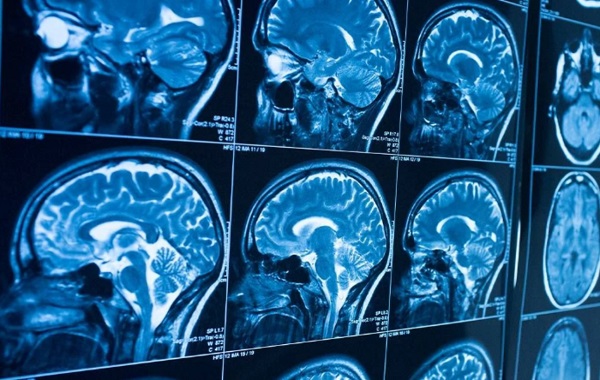

CT cung cấp hình ảnh sọ não chi tiết và rõ ràng